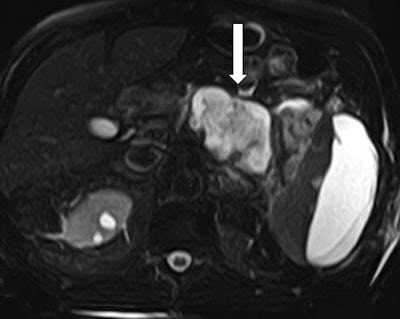

The patient was readmitted two weeks later for fever, abdominal discomfort, and early satiety. On arrival, he was febrile at 38° C and had a pulse of 102 beats per minute, respirations of 25 breaths per minute, leukocytosis of 12,100 white blood cells (WBCs), and lipase of 125 UI-1. He underwent CT scans with IV contrast of the abdomen and pelvis that showed marked mesenteric fat stranding and an acute necrotic collection measuring 4.7 x 13.1 cm within the pancreatic body and tail.

A provisional diagnosis of systemic inflammatory response syndrome (SIRS) was made, after which blood cultures were obtained, and broad-spectrum antibiotics were started and then stopped in 24 hours due to negative blood cultures. MR cholangiopancreatography (MRCP) of the abdomen confirmed a necrotic collection involving most of the pancreatic body and tail (figure 4). The pancreatic duct was encompassed by the collection and difficult to appreciate.